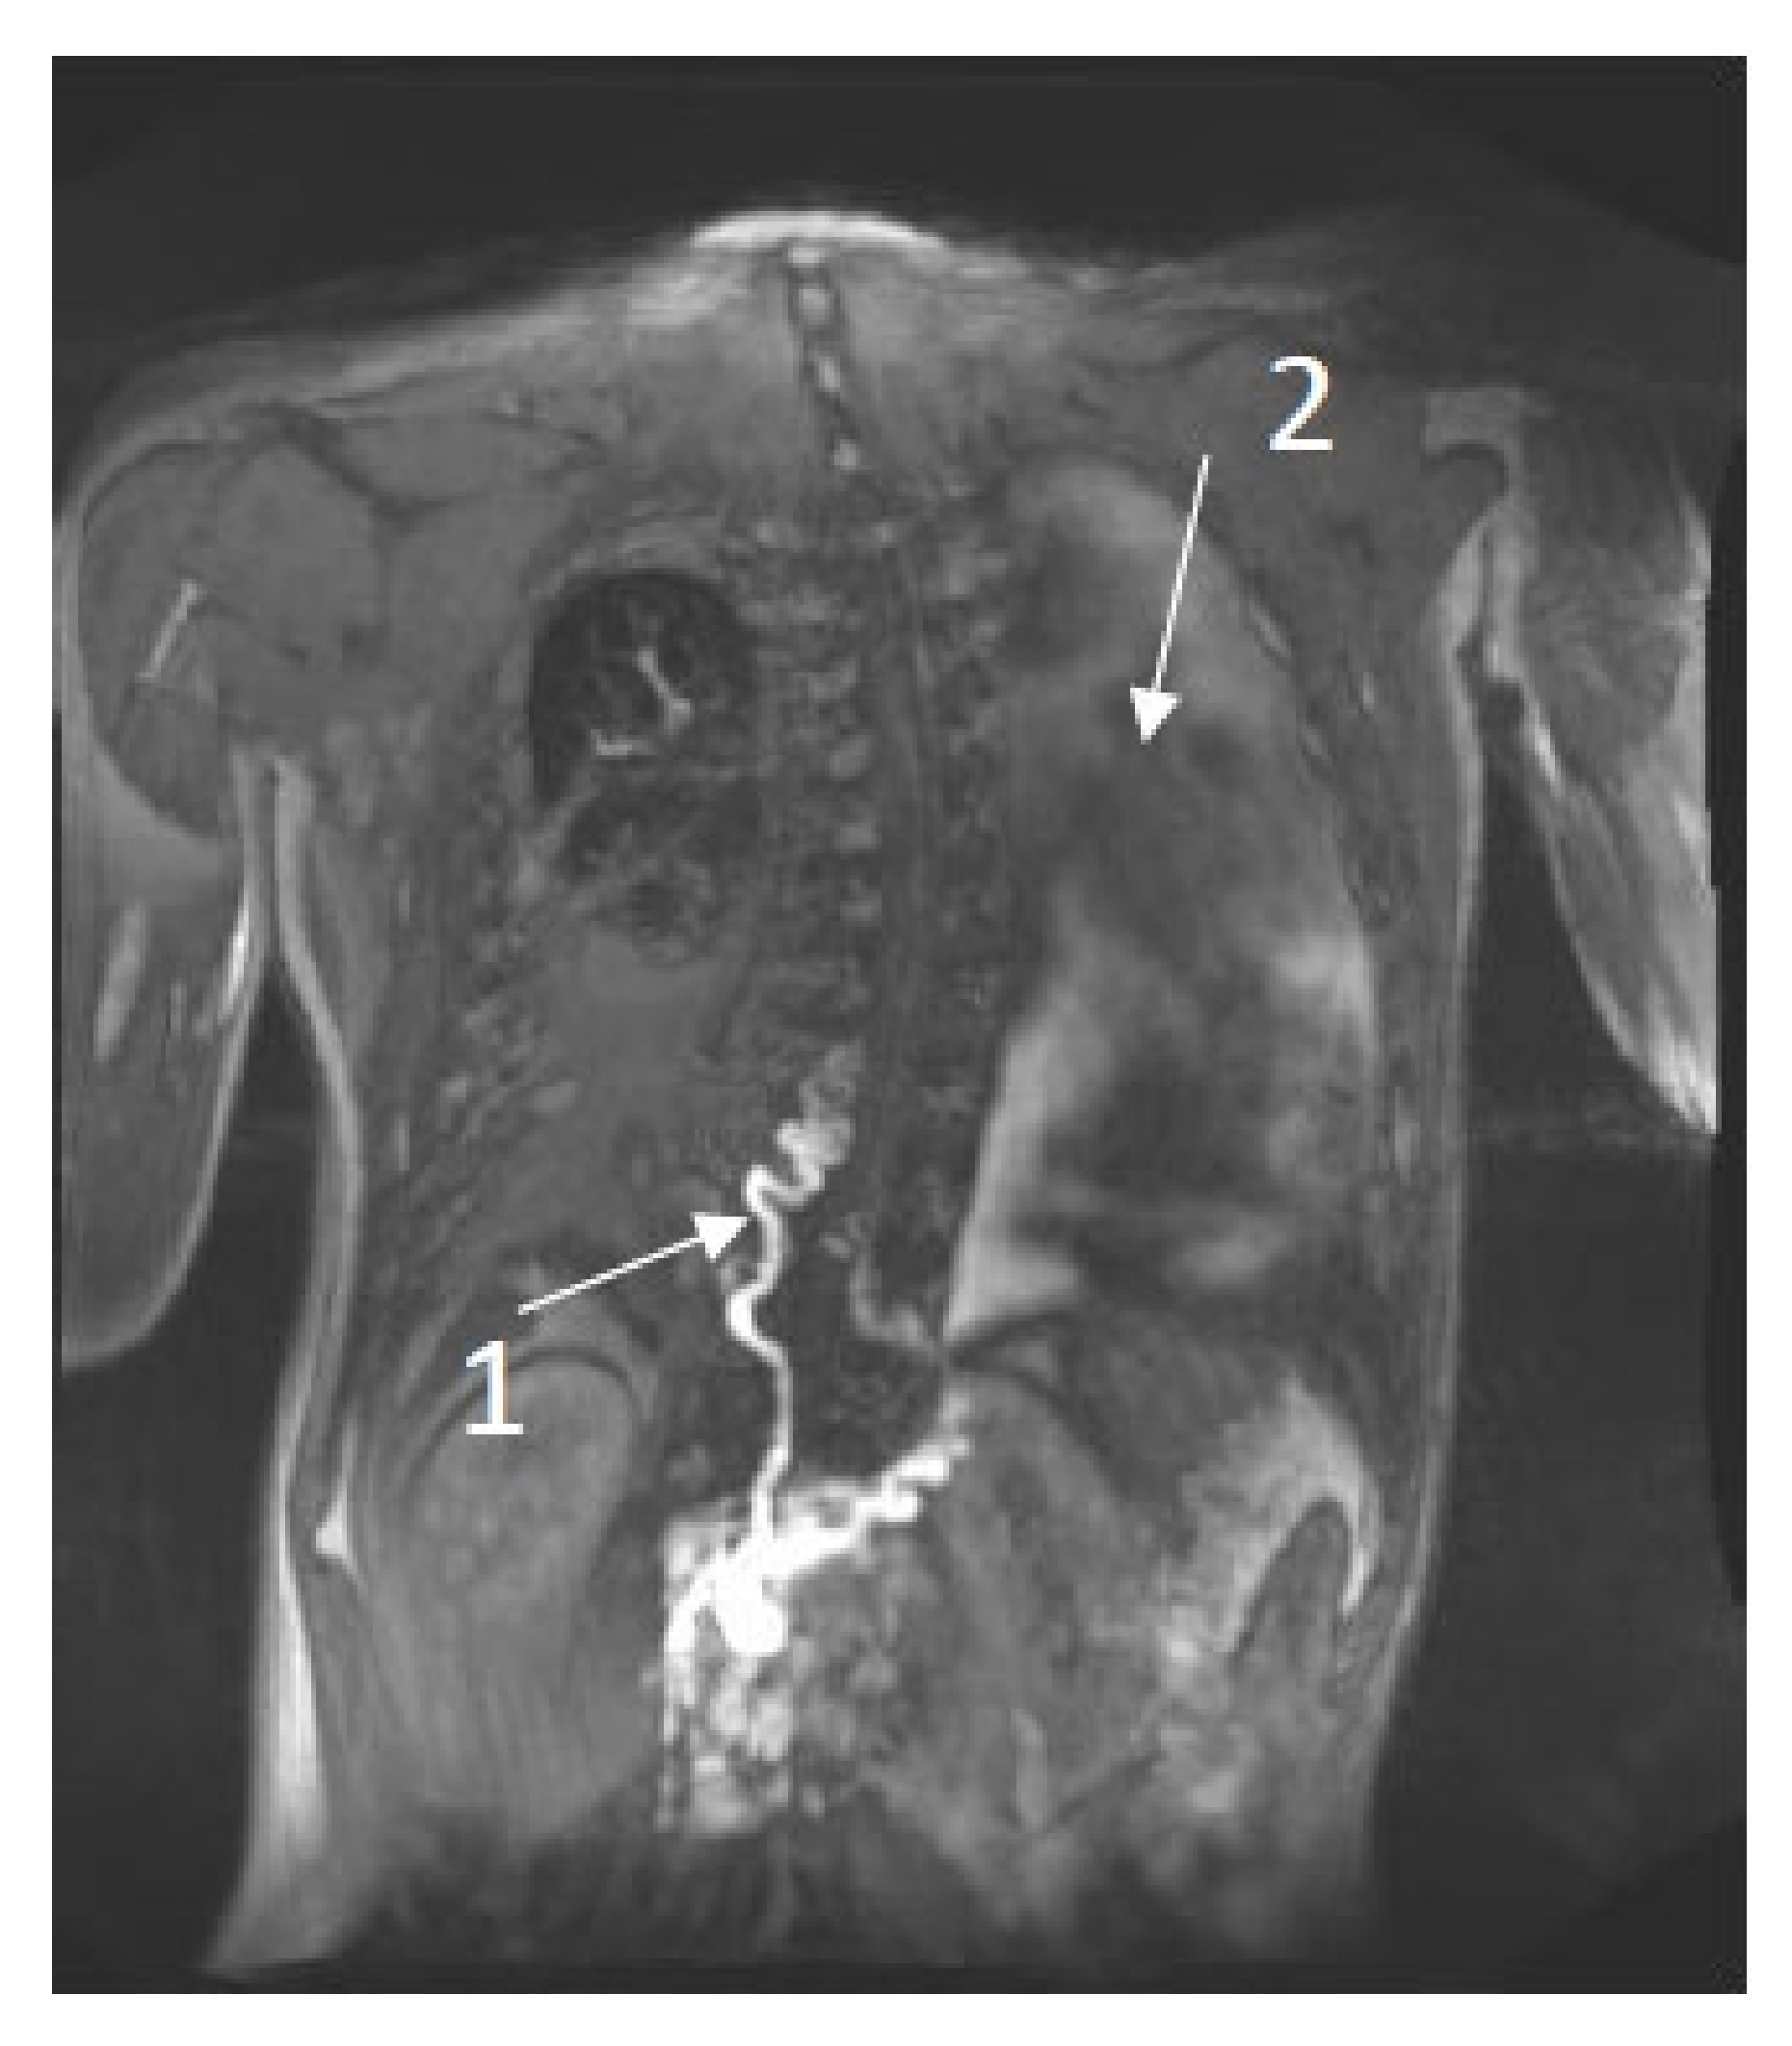

- Chavhan, G.B.; Amaral, J.G.; Temple, M.; Itkin, M. MR Lymphangiography in Children: Technique and Potential Applications. Radiographics 2017, 37, 1775–1790. [Google Scholar] [CrossRef] [Green Version]

- Van Schaik, C.J.; Boer, L.L.; Draaisma, J.M.T.; van der Vleuten, C.J.M.; Janssen, J.J.; Fütterer, J.J.; Schultze Kool, L.J.; Klein, W.M. The lymphatic system throughout history: From hieroglyphic translations to state of the art radiological techniques. Clin. Anat. 2022. [Google Scholar] [CrossRef]

- Itkin, M.; Chidekel, A.; Ryan, K.A.; Rabinowitz, D. Abnormal pulmonary lymphatic flow in patients with paediatric pulmonary lymphatic disorders: Diagnosis and treatment. Paediatr. Respir. Rev. 2020, 36, 15–24. [Google Scholar] [CrossRef] [PubMed]